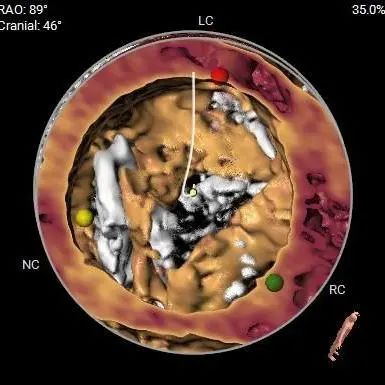

主动脉根部详细情况:

ANNULUS

LVOT

SOV DIAMETER

STJ

AA

瓣环夹角:

瓣上层面分析:

钙化分析:

HU850

钙化分布

冠脉风险:

Left Coronary

LCA & Leaflet

Right Coronary

RCA & Leaflet

三叶式主动脉瓣,瓣叶轻中度钙化并明显增厚,人工瓣膜锚定力尚可,左室流出道呈敞口型,综合多平面分析,预估瓣膜释放后有向下位移风险及瓣周漏可能。

左右冠开口高度稍低,综合瓦氏窦及窦管交界内径综合判断,预估左右侧冠脉阻挡风险适中,术中可根据球扩结果进一步判断,必要时行冠脉保护。